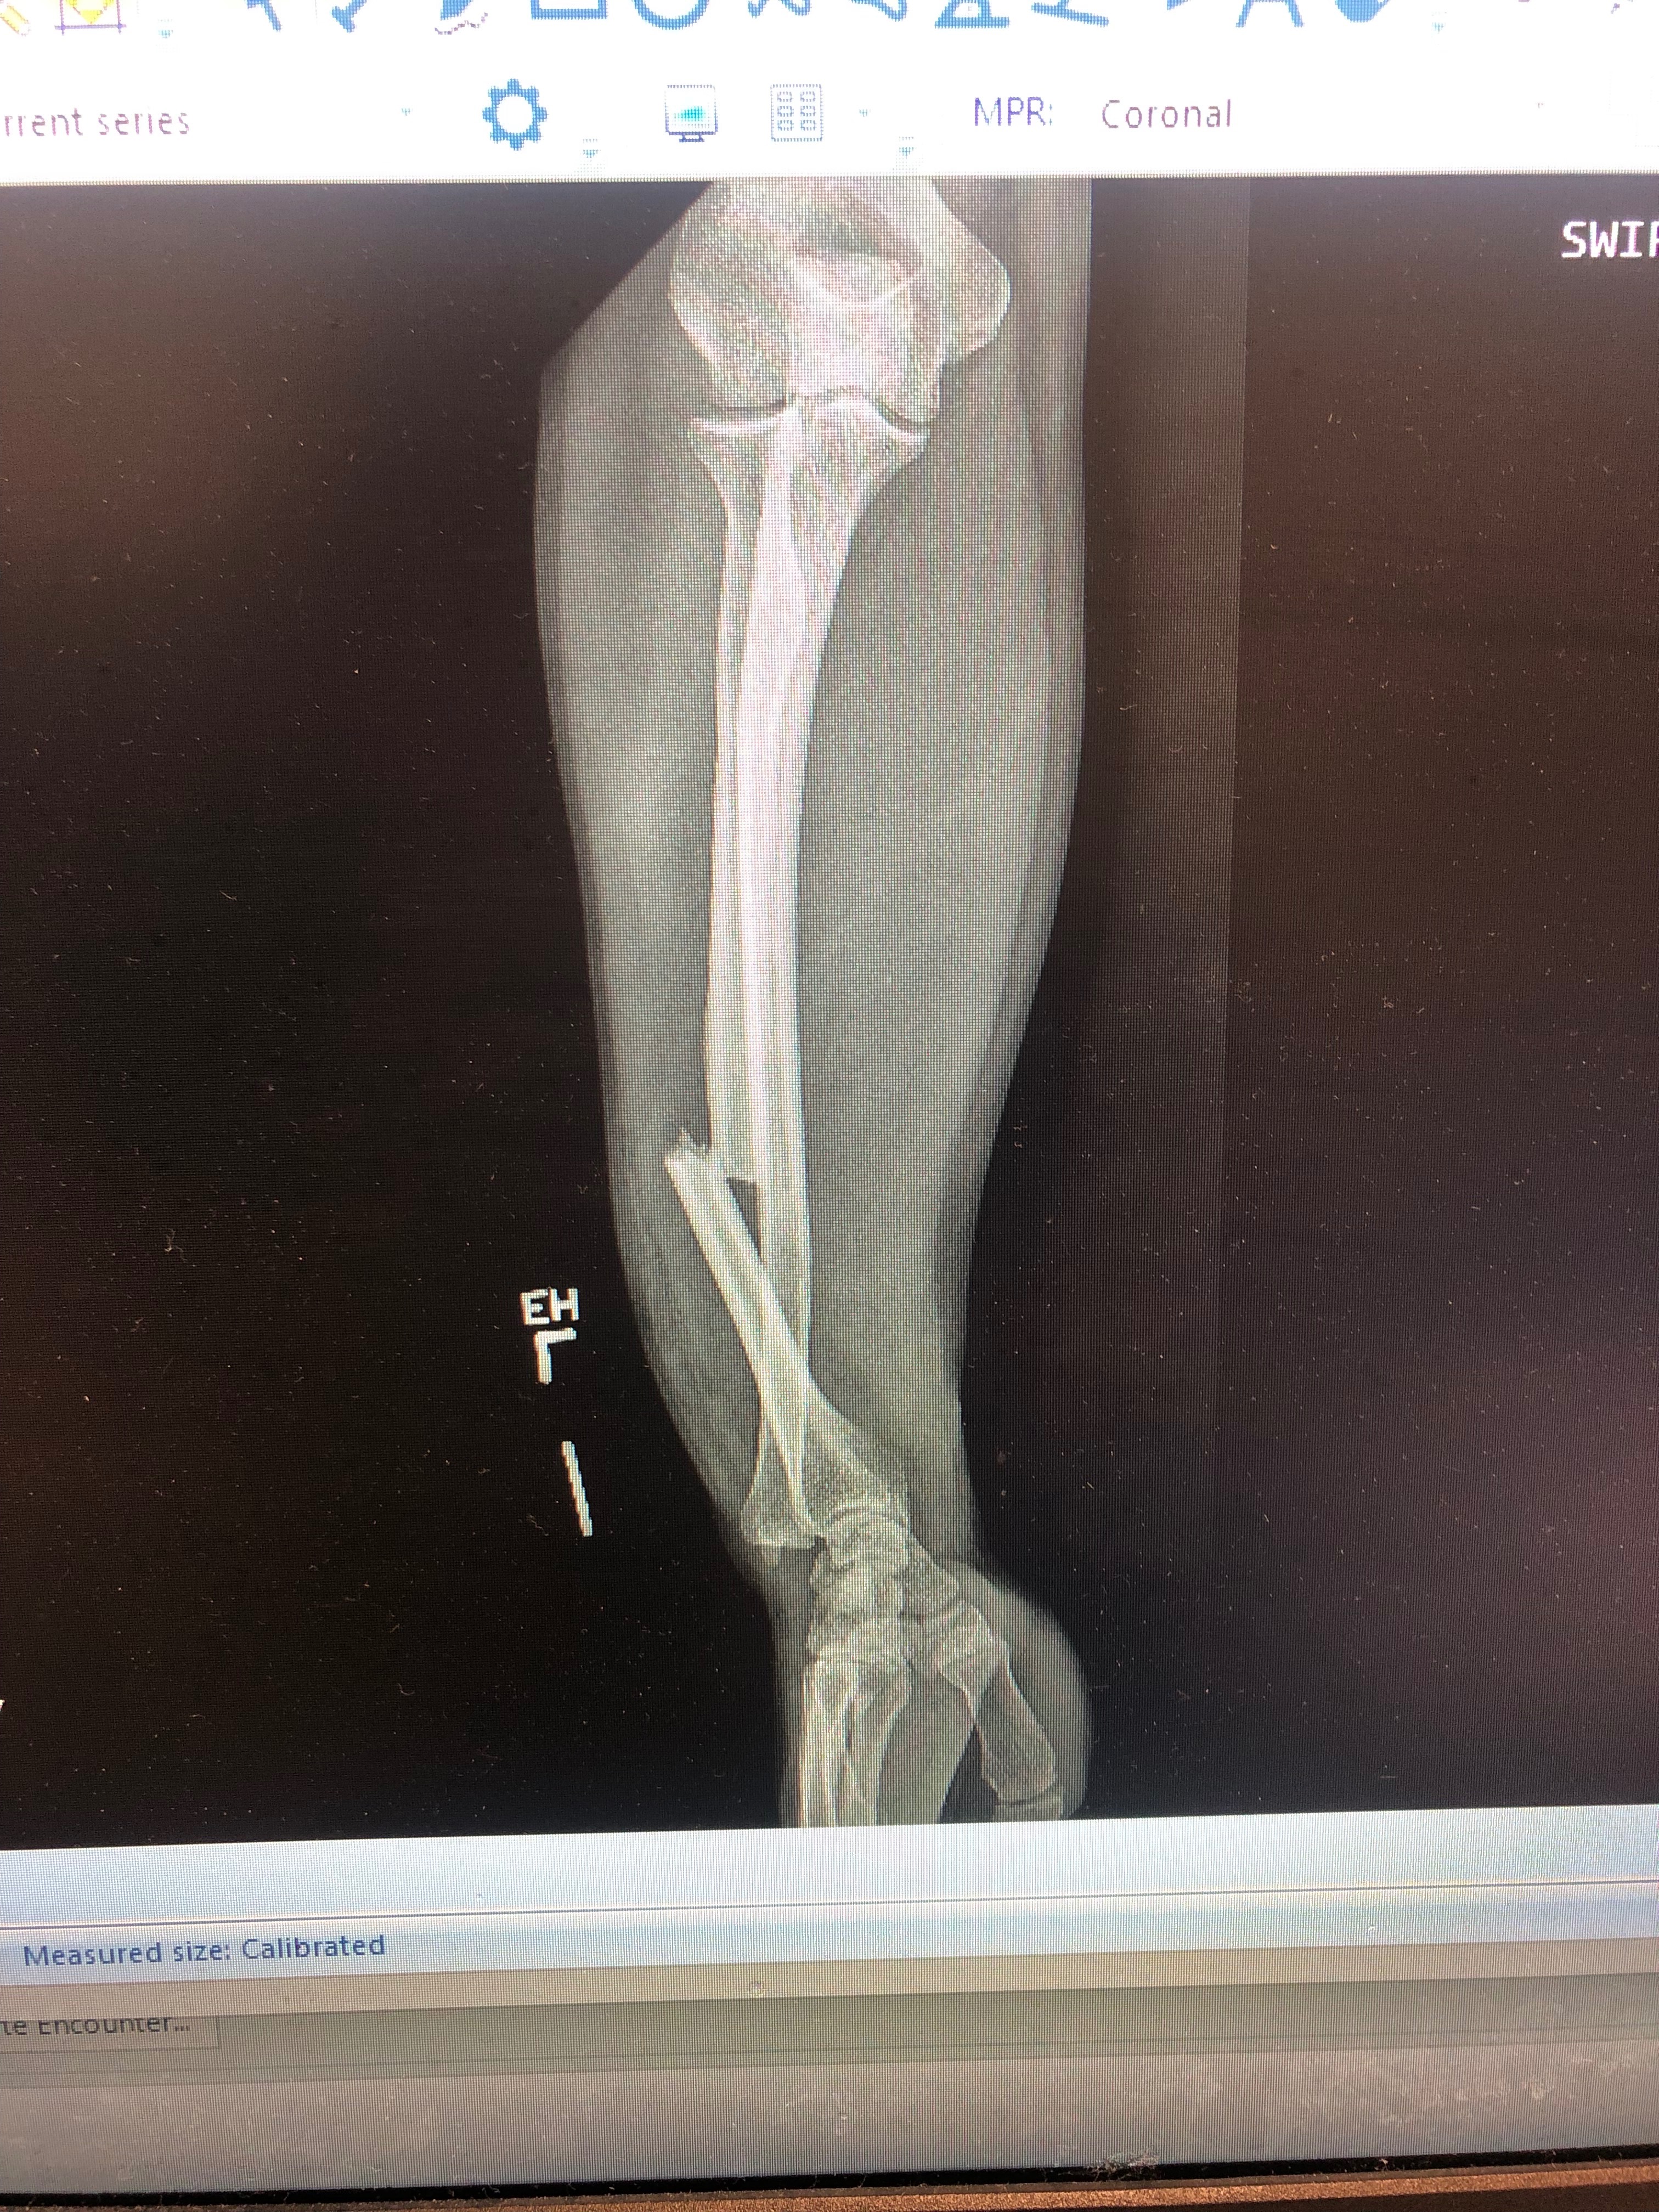

On Wednesday, November 5, I was riding to work in Downtown Houston when I hit a large chunk of concrete that blended into the road surface. The impact threw me off the bike and across the sidewalk, leaving me with a broken left arm.

Because of the injury, I can’t work my waiting job or the supplemental gigs I lined up. Unfortunately, my insurance lands in a gap—it disqualifies me from the hospital’s relief program but doesn’t cover the procedure I need. Thanks to a family connection, I have access to an orthopedic surgeon who has agreed to do the procedure, but I must pay nearly $9,000 up front in order to receive it. Without the surgery, my break won’t heal properly, and I risk being left with a permanent, lifelong disability.